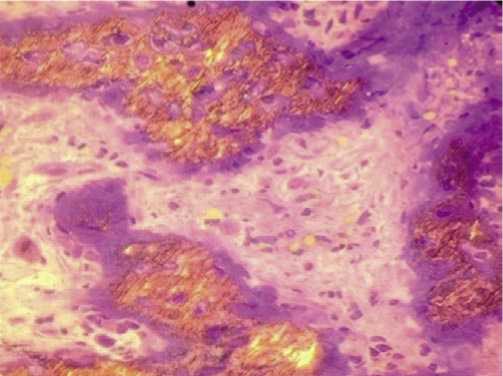

Рис. 3. Выраженная пролиферация остеобластов, фибробластов, васкуляризация и инфильтрация единичными лимфоцитами в образце ткани после туннелизации подвергшейся криовоздействию на протяжении 3 секунд на фоне остеонекроза.

Микроскопически на увеличении 400 выявлена выраженная пролиферация остеобластов и фибробластов, васкуляризация с формированием мелких сосудов капиллярного типа, а также инфильтрация единичными лимфоцитами (Рис. 3).